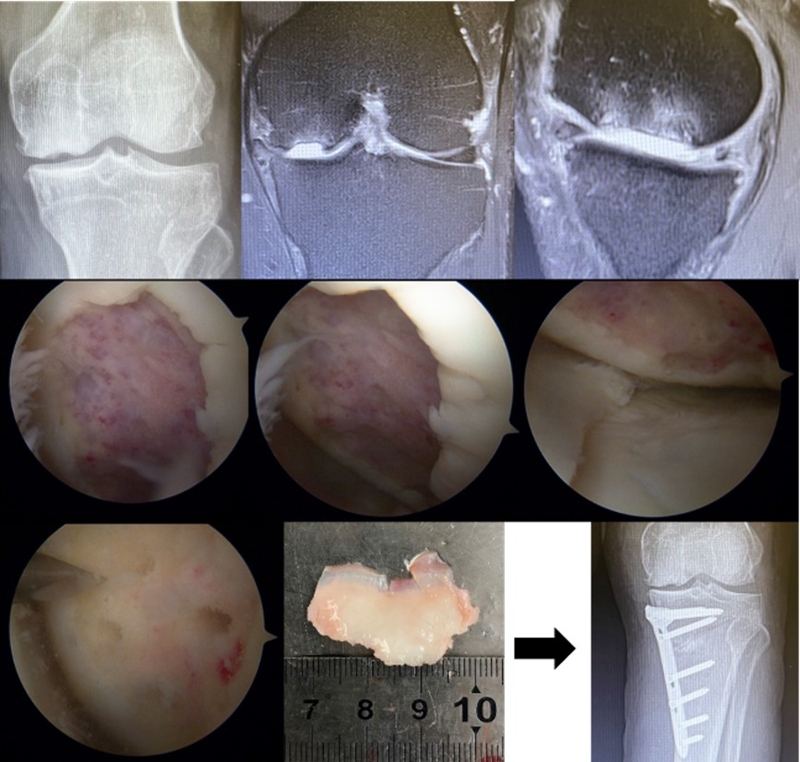

病例1:男,64岁,主诉左膝关节内侧疼痛6年余。MR提示骨坏死区占比为33.28%,矢状位病变区域前后径为26.42mm,半月板相对突出百分比(RPE)31.78%,同时存在胫骨侧来源的下肢内翻畸形(MPTA83°),关节线会聚角2°。

行关节镜检查+软骨摘除+微骨折+HTO术,术后随访2年恢复良好,活动自如,行走时无左膝关节疼痛不适。